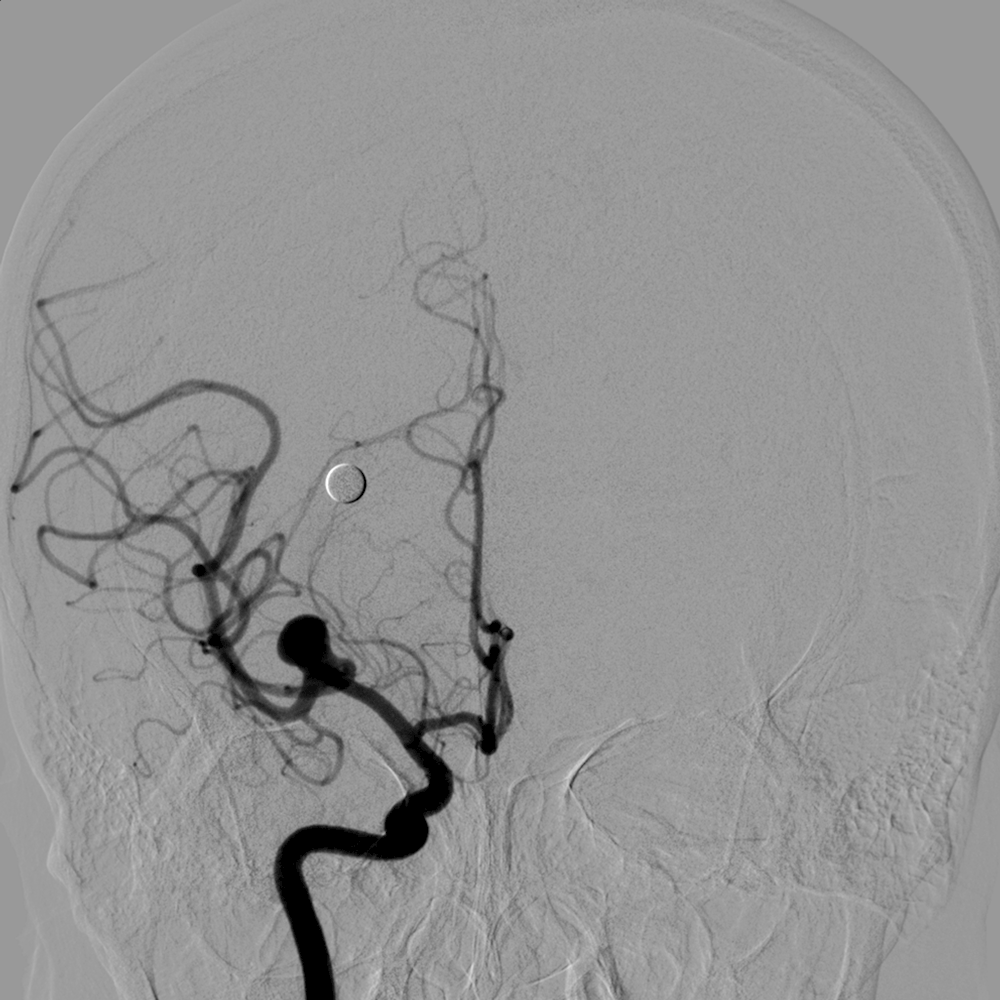

3.神经介入治疗:脑动静脉畸形、脑膜动静脉瘘、脑动脉瘤、脑动脉血栓溶解、脑膜瘤、颈动脉海绵窦瘘等微创介入治疗。

图左:病患右颈内动脉造影显示大脑中动脉有动脉瘤 右侧颈内动脉动脉瘤(红色箭头)

图右:经弹簧圈栓塞后,动脉瘤萎缩消退